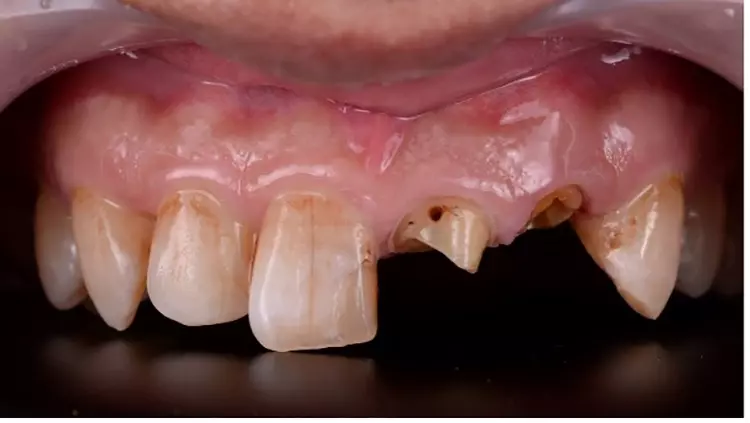

Der 56-jährige Patient stellte sich mit einer dezementierten Krone an Zahn 22 und insuffizientem Zahnersatz an Zahn 21 vor. Die koronale Leakage bestand schon mehrere Tage, bevor der Patient die Praxis aufsuchte. Die Ausgangssituation zeigte, dass beide Zähne zuvor wurzelkanalbehandelt waren (Abb. 1). Nach eingehender Röntgendiagnostik wurde entschieden, die defekte Krone an Zahn 21 zu entfernen und zunächst ein adäquates Kariesmanagement zu betreiben (Abb. 2).

Nachfolgend wurde die Wurzelkanalbehandlung an beiden Zähnen 21 und 22 revidiert und der Zahn 21 mit einem Glasfaserstiftkernaufbau wiederaufgebaut. Zahn 22 wurde im Wurzelkanal oberhalb der Guttapercha-Wurzelfüllung adhäsiv verschlossen und eine Gummiligatur darin vorerst spannungsfrei mit einem adhäsiv haftenden Glasionomerzement, zur farblichen Kontrastierung, eingeklebt. Anschließend wurde ein verblocktes Provisorium der Zähne 21 und 22 auf dem Zahn 21 adhäsiv befestigt und das Brückenteil 22 außer Kontakt geschliffen und nach basal zur Wurzel frei gelassen (Abb. 3). Durch die adhäsive Befestigung wurde das Risiko einer Dezementierung der provisorischen Versorgung möglichst geringgehalten.

Die Aufnahme von palatinal zeigt dabei die Kontaktpunktverteilung und auch das Platzverhältnis zwischen Stumpf und basaler Gestaltung des Brückenglieds (Abb. 4). Eine regelmäßige Kontrolle des Patienten im Abstand von jeweils 1 Woche für eine Gesamtdauer der Extrusion von 3 Wochen wurde in diesem Fall in Abhängigkeit von der Zahnbeweglichkeit als angemessen empfunden. Es musste hierbei ein zusätzlicher Ferrule-Effekt von ca. 1,5 mm generiert werden.